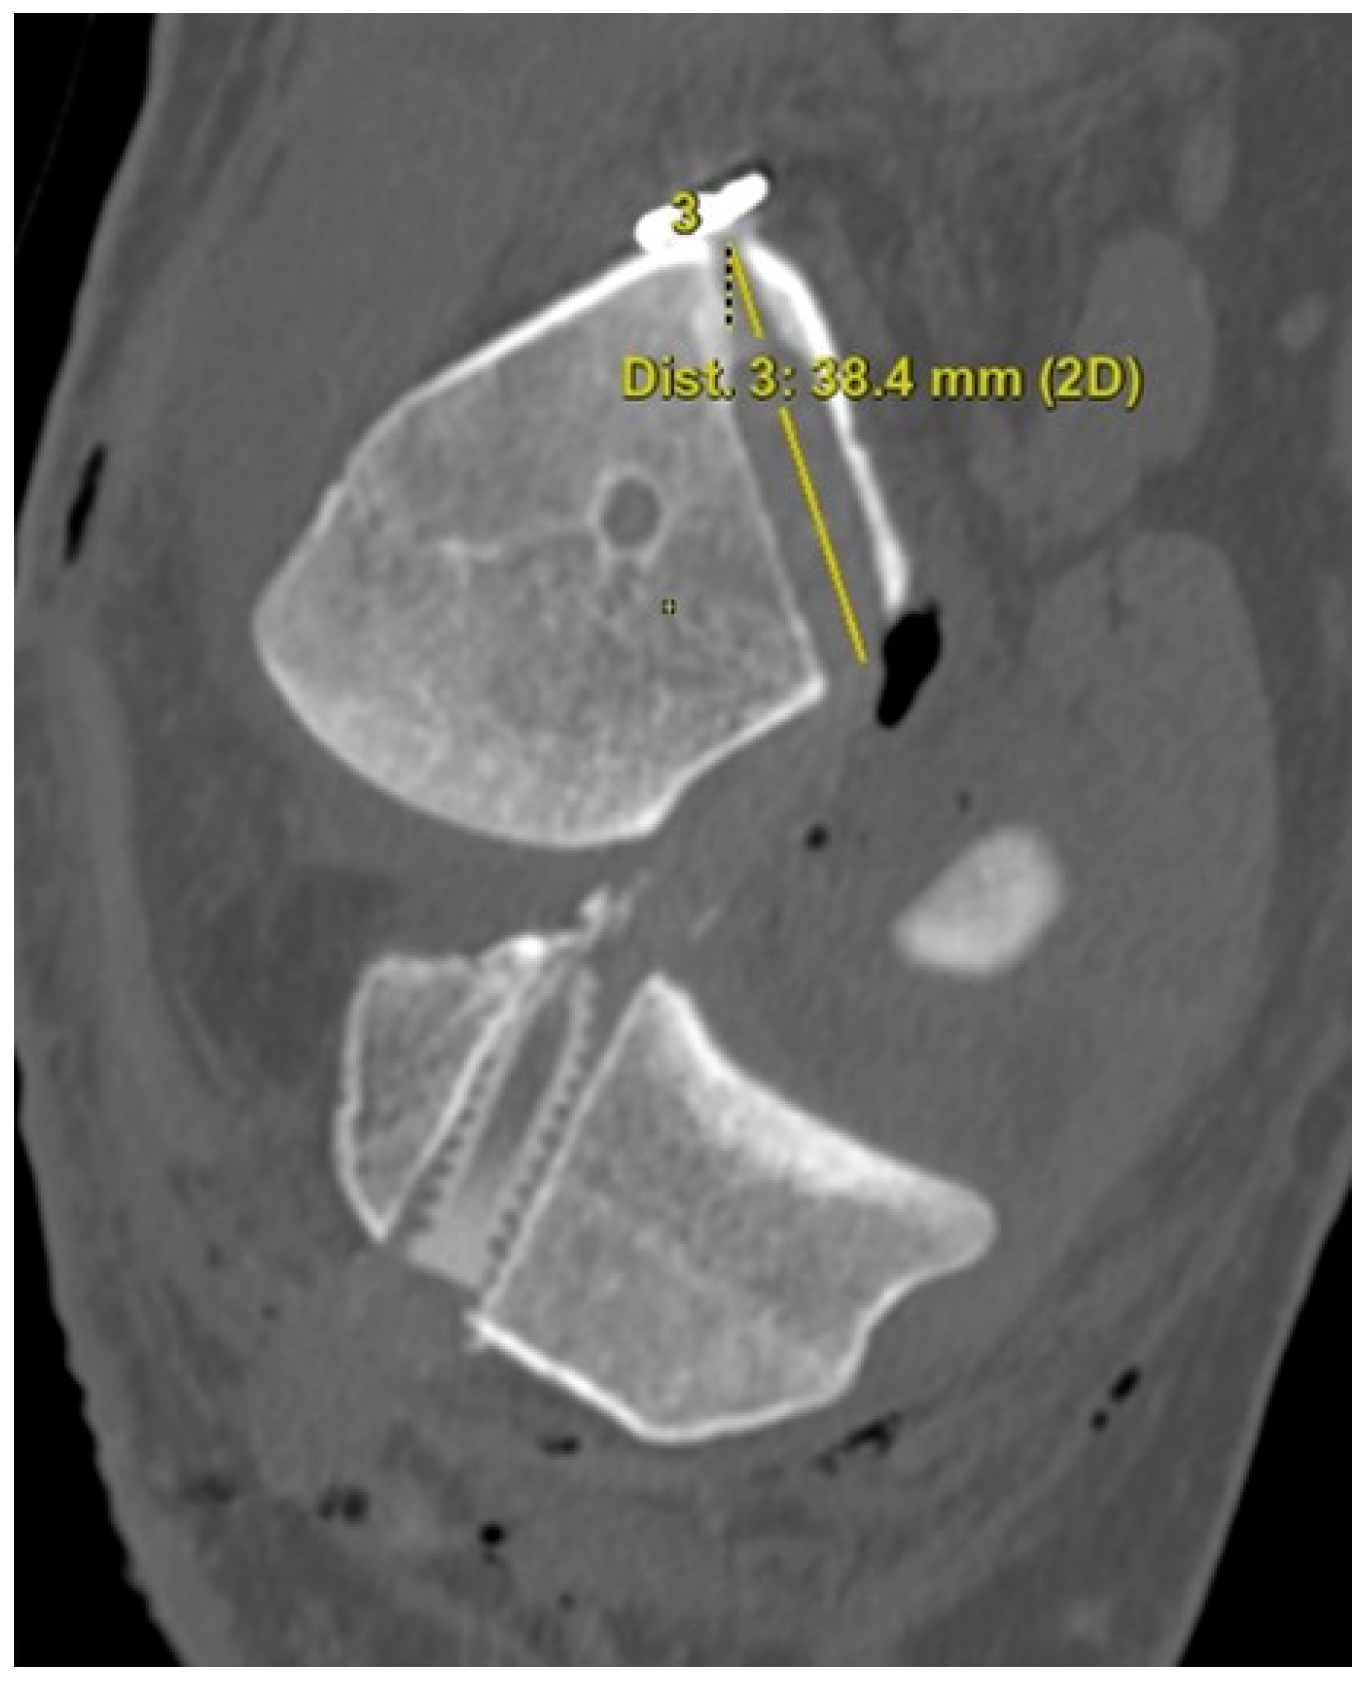

To assess the femoral tunnel location, a true medial view of the lateral femoral condyle with the image of the medial femoral condyle erased at the center of the intercondylar notch was obtained. The quadrant methods used previously by Bernard et al. [23] and Forsythe et al. [24] facilitated the analysis of the femoral tunnel location (Figure 2). The tunnel location was determined in the proximal to distal (deep–shallow) and anterior to posterior (high–low) directions and presented as the percentage of the distance from the posterior edge of the lateral femoral condyle to the roof of the intercondylar notch. The measurements were performed on a picture archiving and communication system (PACS) workstation (Centricity RA 1000, GE Healthcare; Chicago, IL, USA).

Figure 2. The femoral tunnel location is determined in the proximal to distal and anterior to posterior directions and presented as the percentage of the distance from the posterior edge of the lateral femoral condyle to the roof of the intercondylar notch.